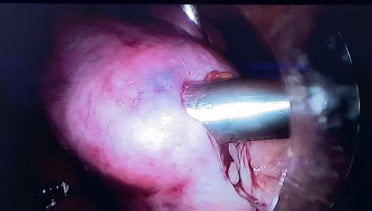

Na laparoscopia, os miomas podem ser retirados pelas técnicas de morcelamento, incisão vaginal ou por uma mini incisão abdominal.

Morcelamento de um útero volumoso